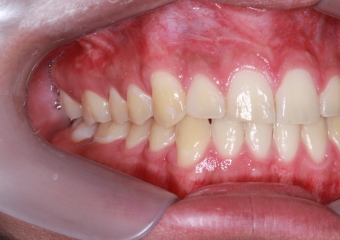

Intra oral com tratamento ortodôntico finalizado 03/16 - Clínica Cliniface

Intra oral com tratamento ortodôntico finalizado 03/16

com tratamento ortodôntico finalizado  - Clínica Cliniface

com tratamento ortodôntico finalizado